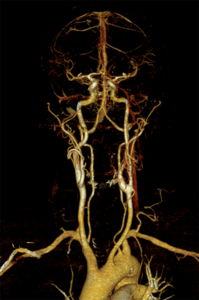

Für die Gefäßuntersuchung steht ein moderner 128-Zeilen-Computertomograf (Siemens Somatom Edge) zur Verfügung. Dieser kann bei einer räumlichen Auflösung von bis zu 0,3 mm kleinste Veränderungen nachweisen. Zur Darstellung der Gefäße wird dazu ein jodhaltiges Kontrastmittel verwendet, welches meist in eine Vene des Armes mit Hilfe einer Spritzenpumpe verabreicht wird. Die Untersuchung selbst dauert weniger als eine Minute.

Aus den dabei gewonnen Schnittbildern sind computergestützte 2D- und 3D-Rekonstruktionen aller Regionen des Gefäßsystemes herstellbar. Dieses Untersuchungsverfahren kommt in unserem Zentrum bei der Diagnostik – Erweiterungen der Bauchschlagader oder andere Gefäße, Durchblutungsstörungen aufgrund von Gefäßeinengungen oder Verschlüssen sowie der Therapieplanung und Therapiekontrolle – zum Einsatz. Einen wichtigen Stellenwert hat die Computertomografie auch bei allen akuten Gefäßerkrankungen und Gefäßverletzungen.

Die Gefäßdarstellung erfolgt in einem modernen 48-Kanal-Magnetresonanztomografen (Siemens Area 48) der mit spezieller Hard- und Software für die Darstellung aller Gefäße des Körpers ausgerüstet ist. Dazu wird überwiegend ein gadoliniumhaltiges Kontrastmittel verwendet, welches meist über eine Armvene injiziert wird. Die Untersuchung dauert ca. 10 – 20 Minuten.

Neben der Erfassung von Veränderungen des Gefäßdurchmessers zur Beurteilung der Durchblutungsstörung, liefert uns diese Untersuchungsform auch wichtige Information zum Aufbau der Gefäßwände, zum Beispiel bei entzündlichen Gefäßerkrankungen und zum Nachweis von durchblutungsgestörtem Gewebe.